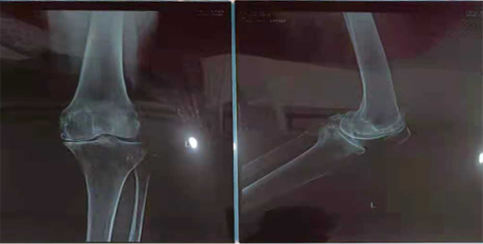

上面,50多岁孔先生的问题是右膝关节患病多年,右膝内侧半月板后角撕裂,医生建议手术治疗,担心后遗症。2021年4月至6月,连续三个月采取关节腔靶向注射间充质干细胞,病痛减轻,目前已经恢复了正常生活。